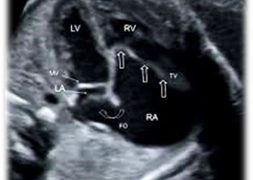

Caso del Mese di Dicembre 2021

Cari soci, finalmente la soluzione del caso del mese di Dicembre! Scarica il File L'attesa è finita: Al seguente link la...